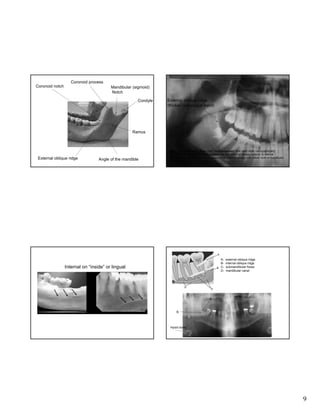

Coronoid process

Coronoid notch

Mandibular (sigmoid)

Notch

Condyle

External oblique ridge

(thicker radiopaque band)

Ramus

Angle of the mandible

Note: External/internal ridges often “superimposed” over each other radiographically;

therefore difficult to differentiate between the two; external always superior to internal

oblique ridge (mylohyoid muscle attachment); internal usually runs below roots of mandibular

molars (see figure 26-62 Haring)

ABCD-

Internal on “inside” or lingual

internal oblique ridge

submandibular fossa

mandibular canal

A

B